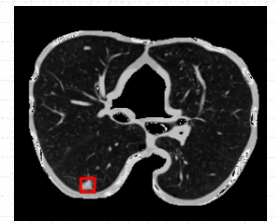

2.1准备数据

关于医疗图像肺结节病灶数据的话,这里本文是利用官方肺结节检测数据集

LUng Nodule Analysis 2016(LUNA16)

进行处理后得到的,已经自己人为标注好了300张病灶数据,可以直接导入华为云ModelArts AI开发平台进行使用。

关于整个肺结节检测数据集的话,数据集文件的大小不大,有35M,共300张已标注好肺结节病灶的文件。